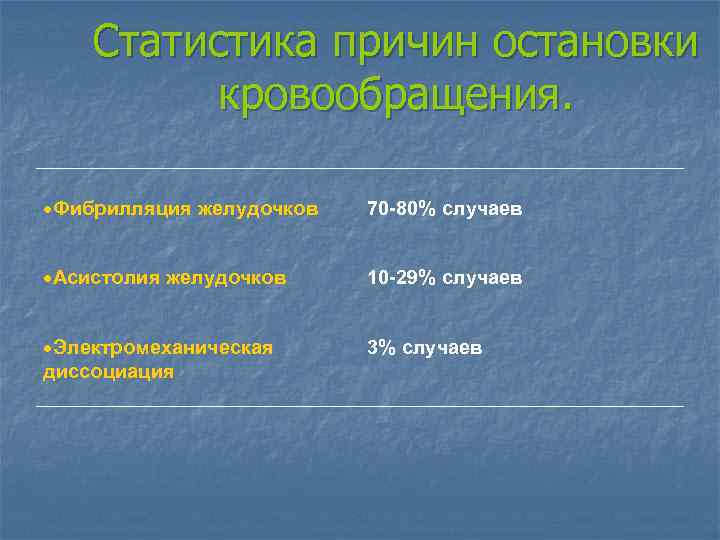

ВИДЫ ПРЕКРАЩЕНИЯ КРОВООБРАЩЕНИЯ w w w Неэффективные сердечные сокращения (идиовентрикулярный ритм, электромеханическая диссоциация). Фибрилляция желудочков. Асистолия желудочков.

Статистика причин остановки кровообращения. Фибрилляция желудочков 70 -80% случаев Асистолия желудочков 10 -29% случаев Электромеханическая диссоциация 3% случаев